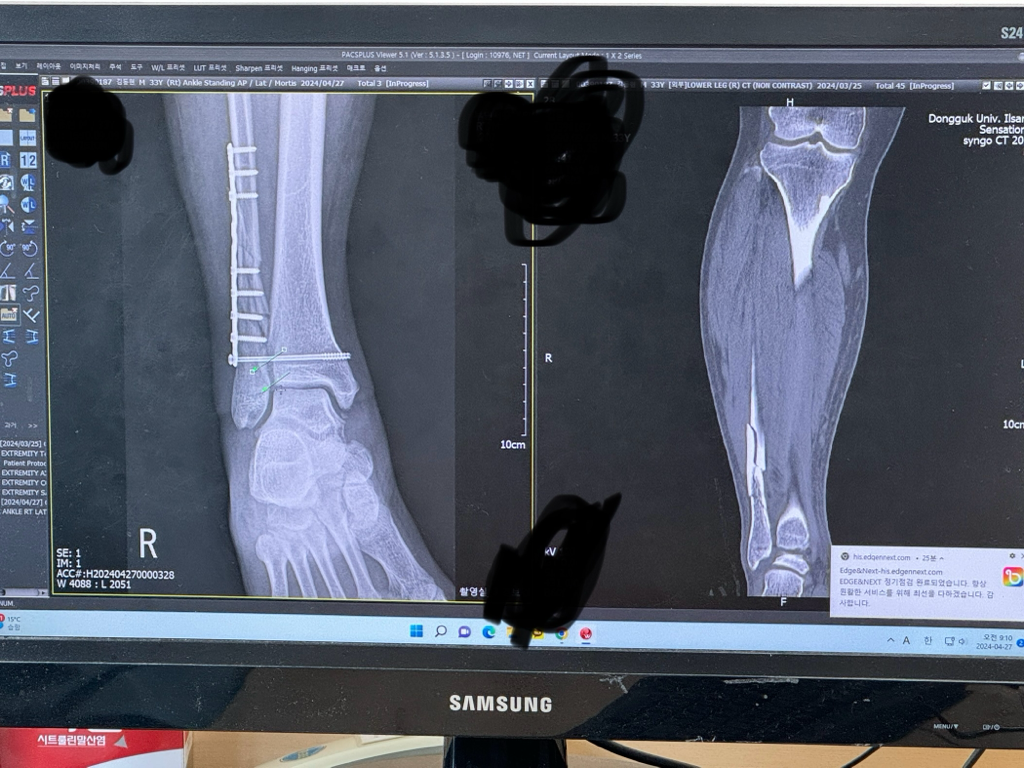

발목 원위부골절 수술 후 문의드립니다

골절 수술 후 6주차 환자입니다.

원위부 비골골절 이후 외래중인데

현재 잘붙고 있다고 이제는 발끝으로는 디뎌도 된다고 하시는데 골진이 안나오는데 뼈가 붙을수 있는걸까요??

사진에 오른쪽은 3월말 골절당시

사진에 왼쪽은 오늘 찍운 사진입니다.